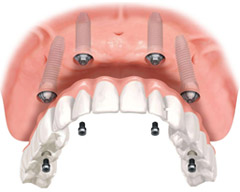

“立得用”突破传统种植牙技术,只需种入4颗(8颗)种植体,就可以恢复半口牙(全口牙)的咀嚼功能,在顾客口腔状态符合的条件下,可以实现,当天戴牙冠吃东西。